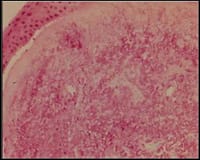

Histopathologically, a pinguecula differs from a pterygia only in location: A pinguecula remains on the conjunctiva (Figure 1), whereas a pterygia actually grows onto the corneal surface. The nodules consist of a mass of abnormal hyaline substance with irregular, dense concretions and curled collagen fibrils (Figure 2).

Figure 2. Histopathology of a pingueculae. |